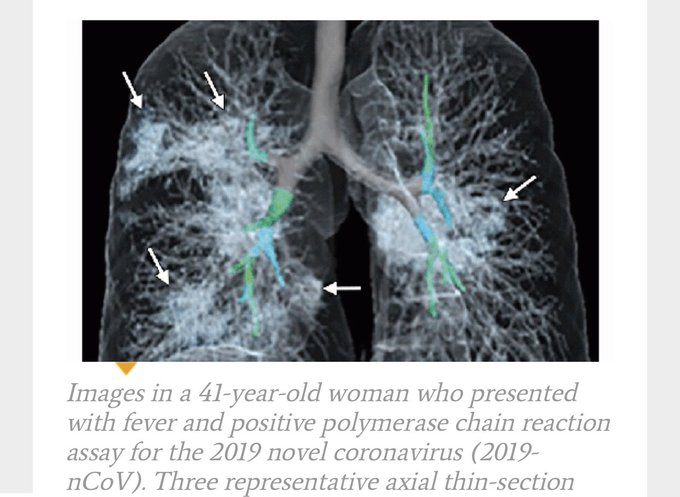

Ernstigere ziekte bij #COVID19 ontstaat als niet alleen bronchitis ontstaat, maar ook een (virale) longontsteking.

Pas bij longontsteking zie je afwijkingen op de longfoto of -scan.

De beelden van de foto’s wisselen, maar in het algemeen ziet men in verschillende longgebieden ontsteking, zoals hier: pic.twitter.com/PeGH8caDbI

De witte gebieden met pijltjes zijn de gebieden van de longontsteking, die op deze foto zwart horen te zijn. U ziet uiteraard ook de bronchieën en de bloedvaten.